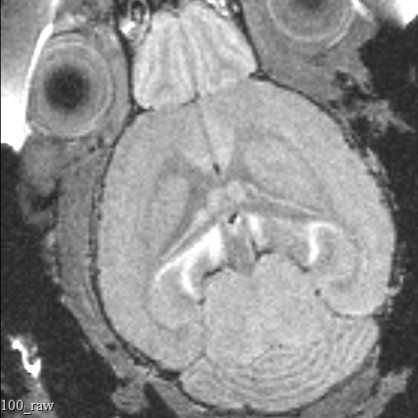

This protocol describes the process of obtaining pre-insertion MRI images using the University of Washington 14T vertical bore Bruker MRI. These structural scans allow for precisely targeting acute electrophysiology recordings in head-fixed mice beyond what is possible using skull landmarks alone.